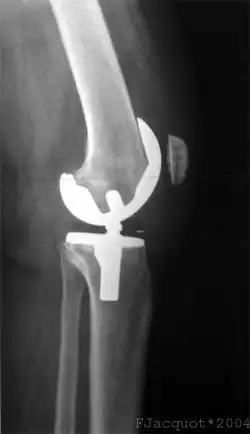

Radiographie d'une prothèse de genou (face).

Radiographie d'une prothèse de genou (profil).